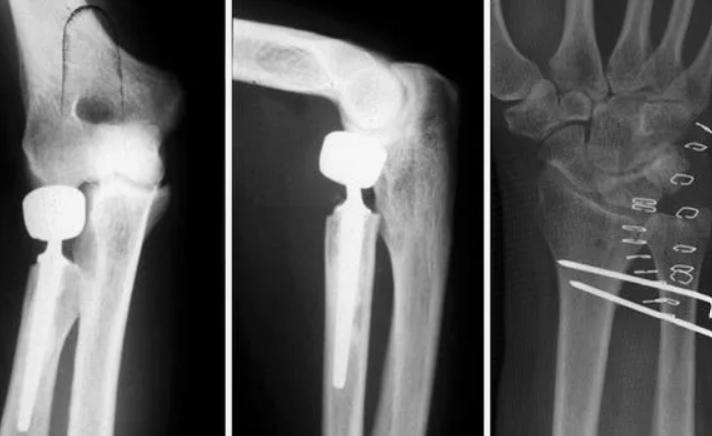

В случае перелома шейки бедра компания МосРентген Центр госпитализирует в Склиф для эндопротезирования.